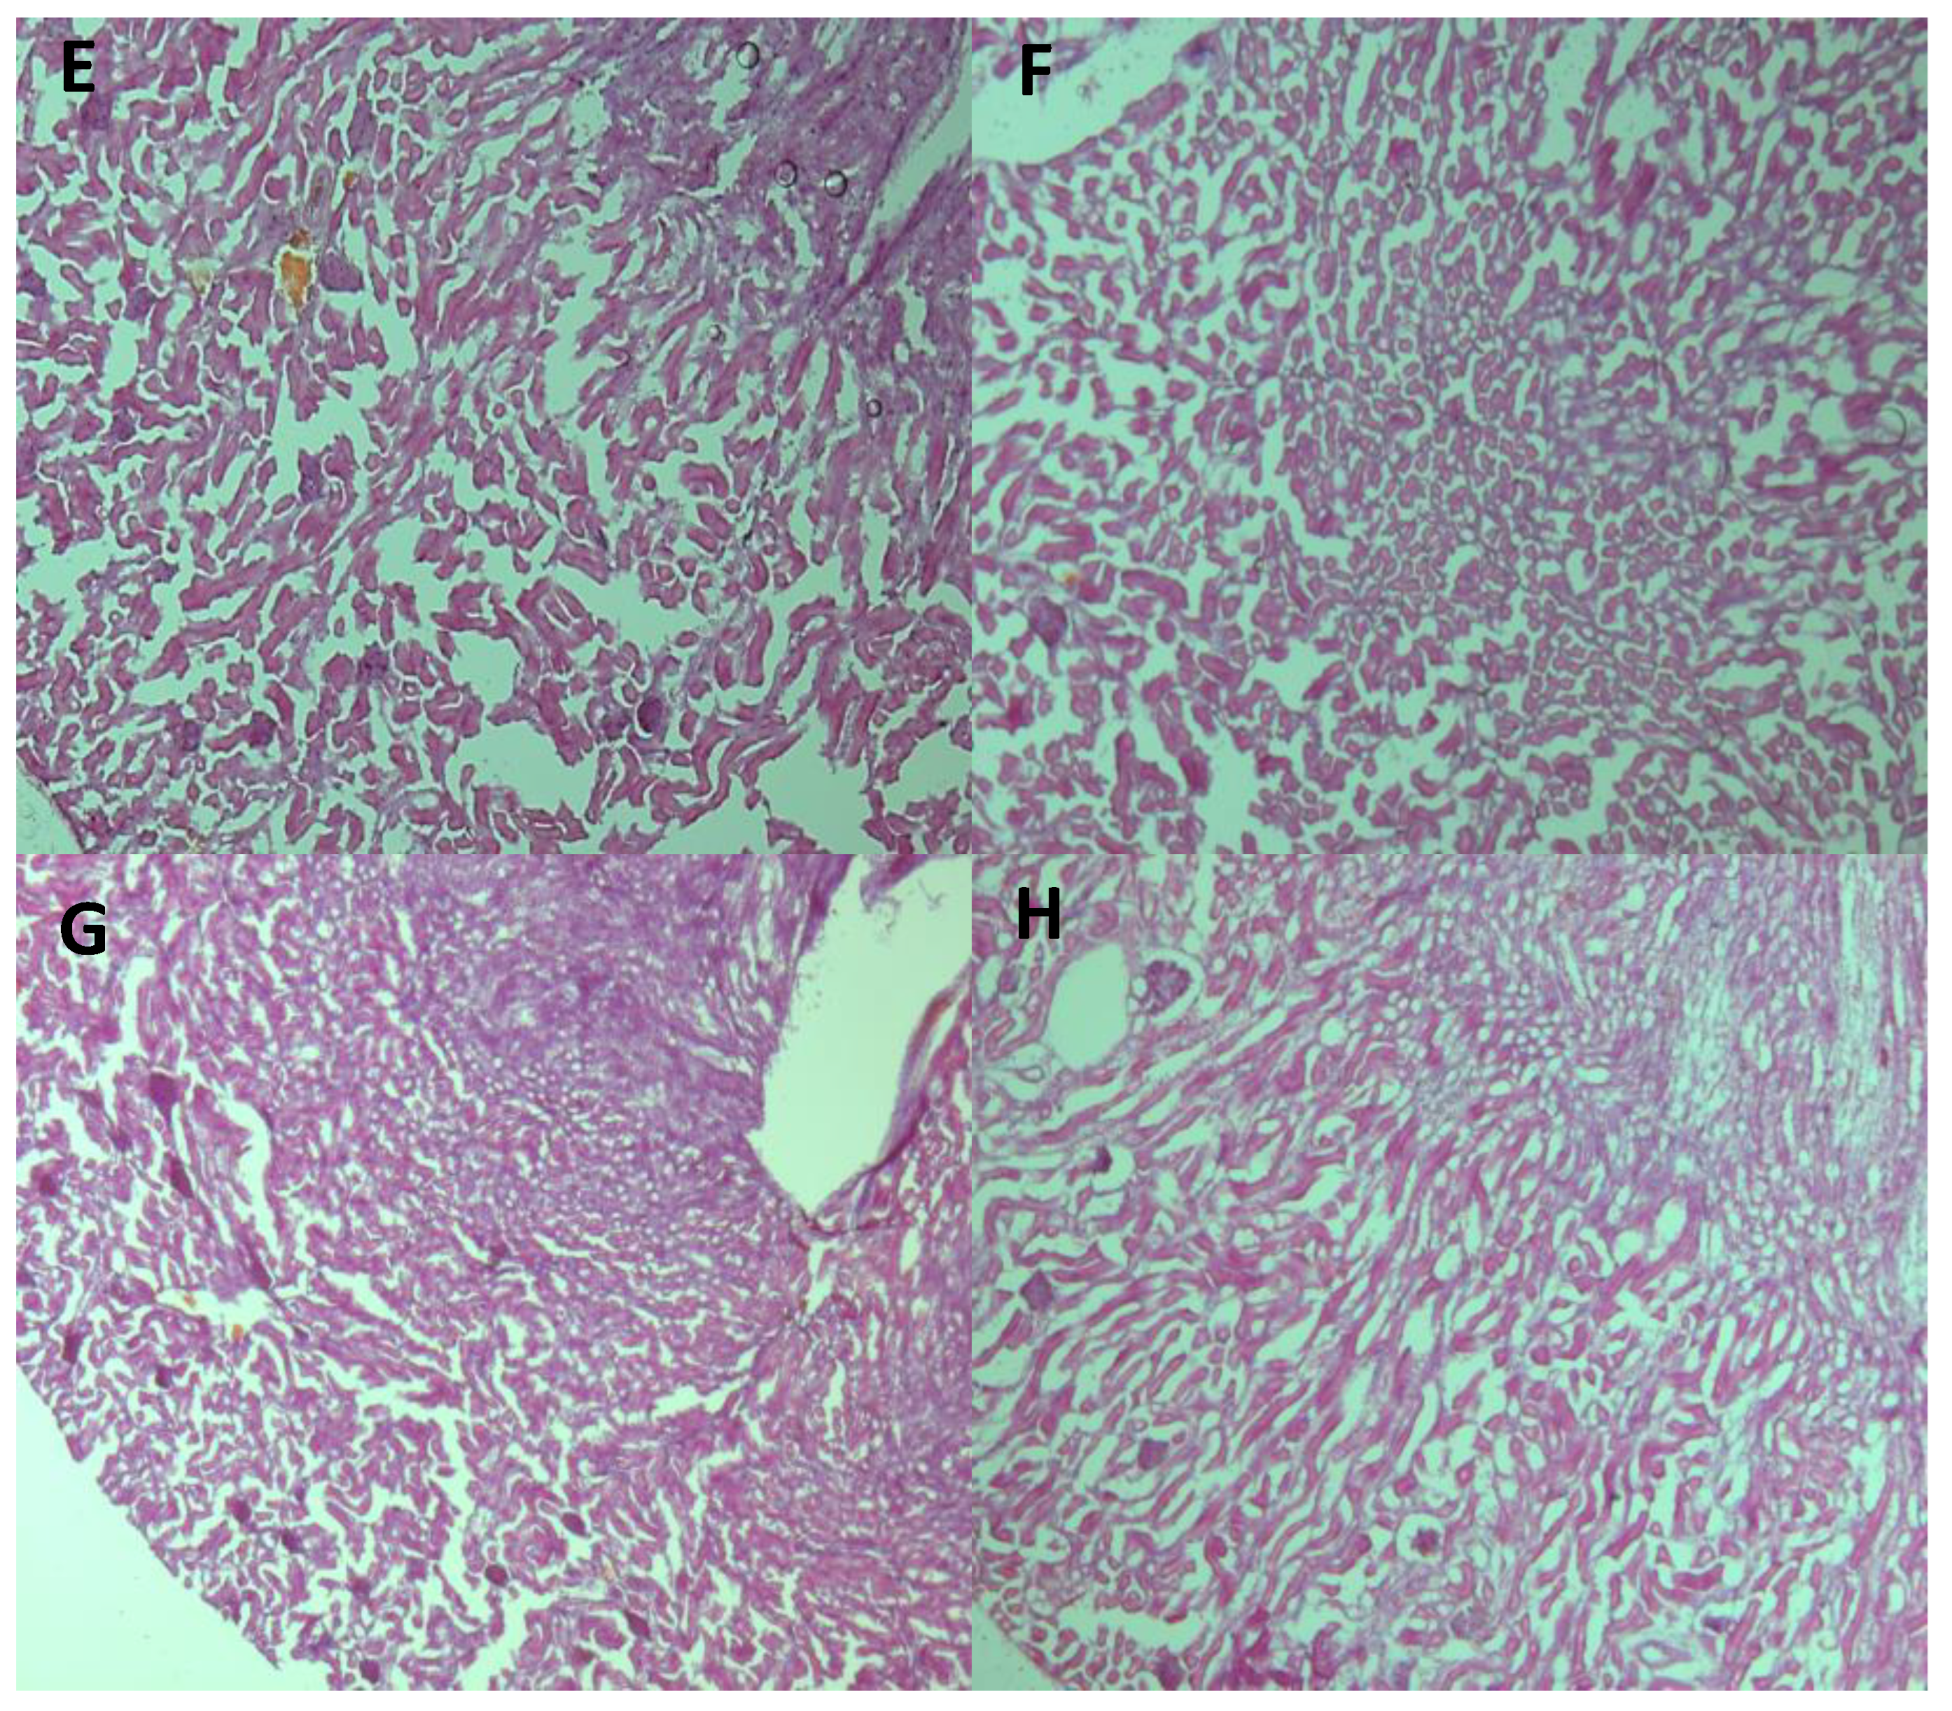

In order to rule out any alterations (toxicity, steatosis, inflammation, or necrosis) caused by BC treatment, a histological analysis was carried out. A qualitative analysis (image comparison Figure 8A–D) showed the presence of steatosis in the UN liver evidenced by white circular spaces [36,37], but the alteration did not appear with BC treatment. Nephron morphology (Figure 8E–H) did not present any alterations among the different treatments; under this type of staining, toxicity damage generates red protein plaques [38], which did not show up.

Figure 8.

Micrograph of 12 μm cuts of liver (A–D) and kidney (E–H), (A,E) from CHOW, (B,F) from CHOW-BC, (C,G) from LPD, and (D,H) from LPD-BC groups. In the (C) (LPD) liver cut, the black arrow indicates the presence of white circles, a distinctive trait of UN steatosis.